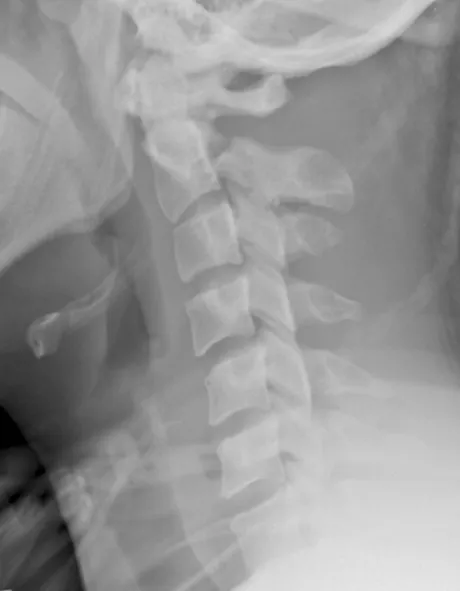

Review the image below [Figure 1]. Describe your findings.

Figure 1.

A lateral radiograph through the cervical spine demonstrates a mild kyphotic angulation at C2/3. There is a fracture through the pars interarticularis of C2. There is 5mm gapping and 12° of angulation of fracture fragments. There is also malalignment of the spinal laminar line, with gapping between the posterior spinous processes at C1/2.

| 1. | Hangman’s fracture (Type II). |

| 2. | In adults, this injury typically results from hyperextension and distraction, as seen in hanging or a high-energy motor vehicle accident (head striking the dashboard). Sometimes in adults and commonly in children, the mechanism is a combination of flexion and distraction as appears to be the case in this example. |

| 3. | The classification system proposed by Levine is most commonly used to organize these fractures: |

| i) | a Type I injury (labeled ‘A’ in Figure 2) consists of a fracture of the C2 pedicles (pars interarticularis), with the fracture line orientated either vertical or near vertical. There is less than 3mm translation and no angulation. The C2-3 disc space remains intact; |

| ii) | in a Type II injury (most common subtype), there is greater than 3mm translation and greater than 10° of angulation of fracture fragments. These fractures are unstable and also demonstrate anterior displacement of the C2 vertebral body. There may also be a compression of the anterosuperior corner of the C3 body (labeled ‘B’ in Figure 2). Type IIa injuries (labeled ‘C’ in Figure 2) differ from Types I and II because the fracture line is more oblique and there is minimal translation but severe angulation. These injuries also have a different mechanism of injury, as they occur due to a flexion distraction force; |

| iii) | Type III injuries are Type II injuries (angulation and translation) with additional bilateral interfacetal dislocation (labeled ‘D’ in Figure 2). There is a higher incidence of neurologic deficits. |